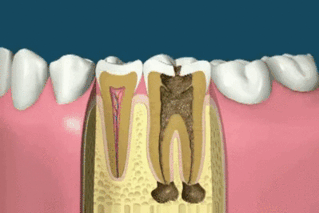

치과치료 고통 사랑니 발치 vs 신경치료

신경치료 할 때는 안아팠는데 짤 보니까 멀쩡하던 이가 아파지는 느낌..ㅠㅠ

아..양치 열씨미 해야겠네여....신경치료 움짤이 너무나 현실적인....